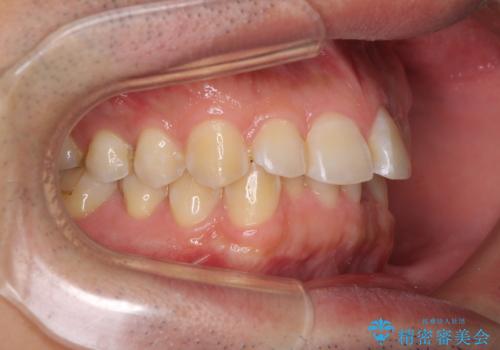

ディープバイトと叢生を解消 インビザライン矯正

ディープバイトが改善されたことで、顎への負担が軽減され、更には上顎前歯の突出感も改善することができました。

矯正治療後には欠けてしまった修復物をセラミックインレーにて修復治療しました。